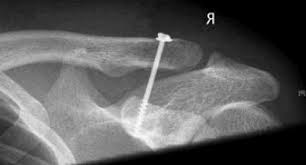

Hình ảnh kết hợp xương khớp cùng đòn bằng vít quạ - đòn